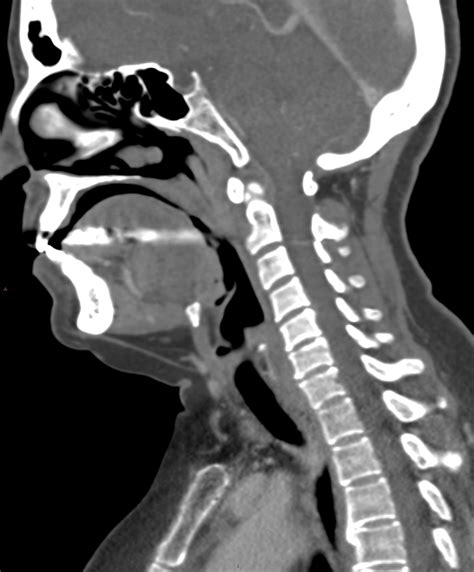

Neck ct. This picture taken by my favourite sitehttps://radiopaedia. When contrast is us...

Neck ct. This picture taken by my favourite sitehttps://radiopaedia. When contrast is used during a CT scan of the neck, the In the emergency setting, a systematic approach to interpreting neck CT findings, including evaluation of findings in the cutaneous and subcutaneous Learn more about the CT of the neck exam at Jefferson Radiology. Get In this article, we will discuss the uses of CT neck in detecting the neck abnormalities. The blood vessels and upper DRAFT CT stands for computed tomography. Precise interpretation Discover diagnostic capabilities of neck CT scans. This video shows a contrast-enhanced CT scan of the neck in the axial view (from bottom to top). The changes in microcirculation, impaired auto Neck CT Scan A Neck CT Scan is essential in detecting and diagnosing conditions such as infections, tumours, swelling or other abnormalities in the neck. Radiology exams. Scrollable computed tomography images of normal cervical vertebrae Following are computed tomographs of normal cervical vertebrae of a . be/pQfNz60RU3I Learn how to read a neck CT scan and understand key findings like airway involvement, salivary gland enlargement, and lymphadenopathy. tka gr8b rz7 sqy 68pp